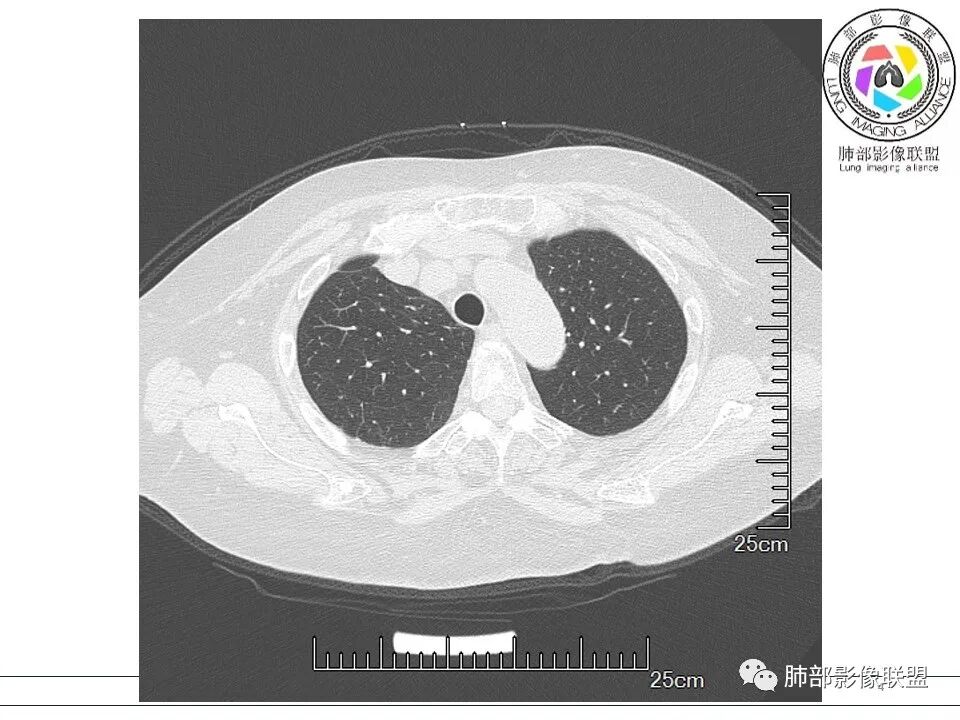

放射小白: 晨读病例:女性,70岁,风湿性多肌痛病史,右肺见不规则结节,边缘及周围见纤维索条影,考虑OP,药物性肺损伤。

小兜: 晨读,女,70岁,风湿性多肌痛病史一年,半月前体检发现肺部阴影,无症状,口服药物治疗。现片示:右肺胸膜下条形实变影,局部层面似见多结节融合,周边伴条索影。下方近叶间胸膜处斑片状实变影伴条索影,宽基底与胸膜相连。综合考虑为炎性病变,隐球菌或OP可能

宇宙: 右肺上叶胸膜下结节,多结节融合,长轴平行胸膜,边缘模糊,周围长索条,胸膜牵拉,近端支气管充气扩张,考虑隐球菌,鉴别OP

玫: 晨读:右肺上叶胸膜下软组织密度影,边缘模糊,周围见条索影及少许磨玻璃影,轻度胸膜牵拉,考虑炎性病变。

金豆 (刘权威): 右肺上叶胸膜下团块,支气管充气征,边缘纤维索条,磨玻璃,OP。

果哣.: 右肺上叶靠近胸膜结节影,平直为主,边缘清晰,支气管进入后截断,有扩张,考虑炎性隐球菌可能

衡妈: 老年女性,右肺上叶沿胸膜下不规则实性病灶,长轴平行于胸膜,有结节融合感,边缘部分彭隆部分平直,周围可见数条纤维灶影,病灶内可见充气支气管征未达远端,首诊考虑慢性炎性肉芽肿,隐球菌?机化性肺炎?建议增强扫描及ct下穿刺活检。

放射线 (王秀仙): 右肺上叶胸膜下结节样影,边缘平直收缩,胸膜牵拉,支气管进入病灶并扩张,部分支气管进入后阻塞,长轴平行于胸膜,周围可见片状及条索状影,隐球?机化性肺炎?

晨读:女,70,未诉症状。风湿性多肌痛病史,口服强的松等药物治疗。胸部CT:右肺上叶多发不规则斑片影,沿支气管分布,部分病灶侧向融合、平行于胸膜,边缘平直内收为主、部分彭隆,周围模糊晕、可见数条纤维灶影,胸膜牵拉,病灶内可见充气支气管征、管腔不畅,考虑慢性炎症,PC?OP?鉴别腺Ca、SCLC等。

瑞欣 (刑瑞欣): 晨读,老年女性,右肺上叶不规则高密度影,可见胸膜牵拉,边缘光滑平直,与胸膜平行,周围条状影,可见支气管充气征,有风湿病史,考虑机化性炎症,鉴别隐球菌,腺癌

良孑: 右肺胸膜下多发结节,长轴与胸膜平行,部分病灶有多结节融合,可见近端支气管充气征,有晕征及晕中软毛刺,长期口服激素病史,抗炎效果欠佳。病灶形态单一,无播散性树芽,结节内无支气管穿行,单侧发病,收缩力差,可排除TB,OP及淋巴瘤,综和考虑支持隐球菌

5、分布:隐球菌肺炎是肺泡性炎症,病灶分布多位于胸膜下,可紧贴胸膜,也可与胸膜邻近,病灶长轴与胸膜平行。(划重点,分布特点非常重要,因为隐球菌如果没有荚膜,会被巨噬细胞吞噬,在人体内是无法生存。隐球菌孢子吸入后,要有高浓度的CO2的条件下,才能形成荚膜,所以肺泡内、胸膜下多见)